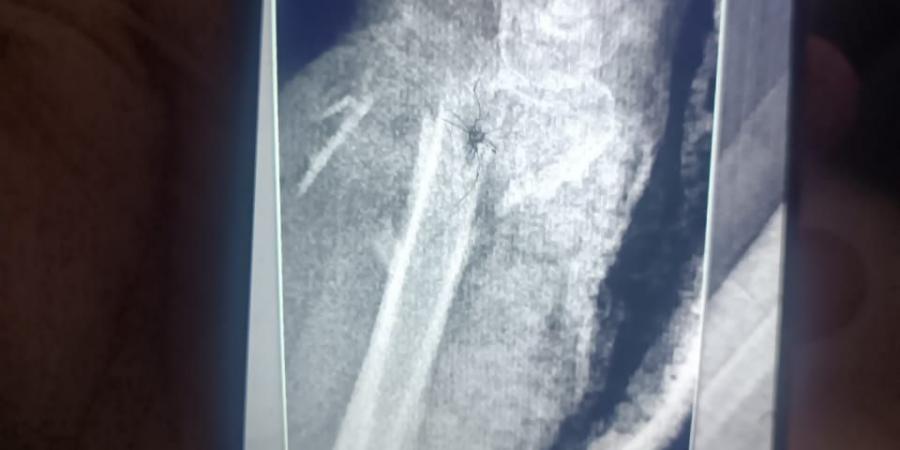

نجح فريق طبي بمستشفى الفيوم العام في إنقاذ حياة سيدة تبلغ من العمر 65 عامًا، عقب تعرضها لسقوط من ارتفاع أدى إلى إصابات بالغة وخطيرة في اليد والساعد، في واحدة من أدق التدخلات الجراحية التي تشهدها المستشفى.

وأكدت الدكتورة نيفين شعبان، وكيل وزارة الصحة بالفيوم، أن مستشفى الفيوم العام، بقيادة الدكتور محمد عبد الله، استقبلت الحالة وهي تعاني من تهتك شديد بالجلد، وقطع كامل بالأعصاب والأوتار في منطقة الرسغ، مع تأثر بالغ بالدورة الدموية لليد، نتيجة كسر مضاعف بعظام الساعد، ما شكّل تهديدًا حقيقيًا بفقدان اليد.

وبدأ التدخل الجراحي بقيام فريق جراحة العظام بتثبيت الكسر المضاعف بدقة عالية، لضمان استقرار العظام وتهيئة الحالة لاستكمال التدخل الجراحي الدقيق.